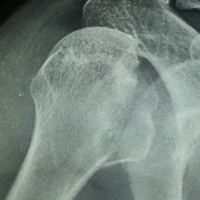

Case:9 Comminuted Intertrochanteric Fracture

Patient aged 75 years with Comminuted Intertrochanteric fracture treated with closed reduction & Ender’s nailing.

Pre-op Ap

Pre-op Lateral